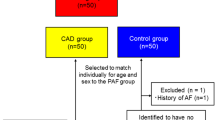

From 4311 patients who were hospitalized at Montefiore between March 1st and June 23rd, 2020, with confirmed COVID-19 by PCR, we identified 504 patients who had a non-contrast chest CT performed during or within 5 years prior to admission. A total of 125 patients were excluded, 114 due to prior AF, and 11 due to uninterpretable CT. A total of 379 patients were finally included for analysis. Overall median age was 68 (IQR 58–76) years, 48.3% were male, and 39.3% Hispanic. Diabetes (DM) (59.9%), hyperlipidemia (70.7%), and hypertension (86.8%) were highly prevalent, whereas CAD and asthma/COPD were present in < 50% of patients (39.8 and 49.5%, respectively). There was no difference on CHA2DS2-VASc score between the group without and with new-onset AF (4 [3,4,5] vs 3 [2,3,4]; p = 0.818). On average, patients presented to the hospital 2 days after onset of symptoms (IQR 0–5). There were 16 episodes of new-onset AF (4.22%) detected during hospitalization. Patients who developed new-onset AF were more likely to be male (75.0 vs 47.1%; p = 0.029). There were no differences in age (68.0 [56.3–70.5] vs 68.0 [58.0–76.0] years; p = 0.712), BMI (28.5 [25.3–30.8] vs 26.9 [23.1–31.8] kg/m2; p = 0.283), or prevalence of DM (56.3 vs 60.1%; p = 0.761), hyperlipidemia (87.5 vs 70.0%; p = 0.132), hypertension (75.0 vs 87.3%; p = 0.154), CAD (50.0 vs 39.4%; p = 0.396), or asthma/COPD (37.5 vs 49.0%; p = 0.366). On presentation, there were no significant differences on vital signs (Table 1). There was a small difference on serum potassium levels (4.7 [4.4–5.7] vs 4.4 [4.0–4.9] mEq/l; p = 0.027) but not on other routine laboratory tests at the time of presentation. Patients who developed AF had worst outcomes with longer hospitalization (Fig. 2; 15 [8–26.8] vs 6 [4,5,6,7,8,9,10,11,12] days; p < 0.001), requirement of pressors (75 vs 22%; p < 0.0001), and intubation (81.3 vs 22.0%; p < 0.001). Patients with new-onset AF were more likely to receive IV steroids (56.3 vs 25.5%; p = 0.005) but there were no differences on use of inotropes (0.0 vs 1.4%; p = 0.637), hydroxychloroquine (75.0 vs 64.5%; p = 0.387), chloroquine (0.0 vs 1.9%; p = 0.575), azithromycin (37.5 vs 29.2%; p = 0.476), or antibiotics (93.8 vs 80.2%; p = 0.177).